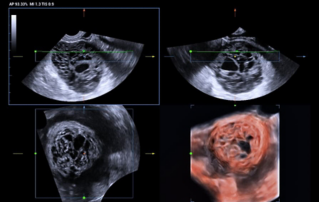

Comprehensive overview of granulosa theca cell tumors of the ovary, covering epidemiology, clinical presentation, diagnosis, treatment options, and prognosis for both adult and juvenile types.